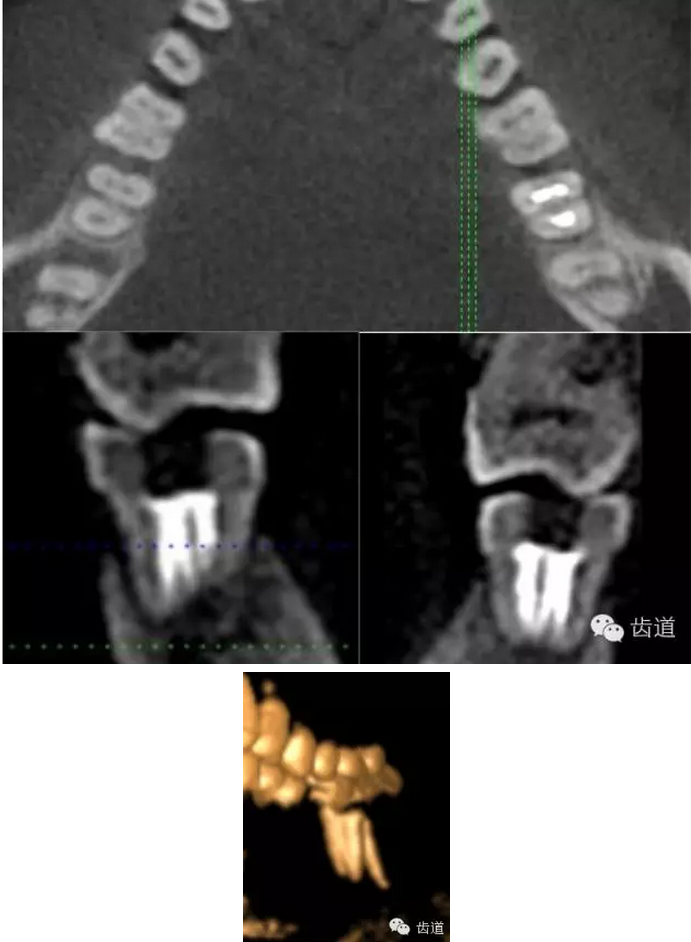

下頜第一磨牙:為3-4個(gè)根管,遠(yuǎn)中雙根管的發(fā)生率為51.4% 左右,側(cè)支根管發(fā)生率為30%左右;